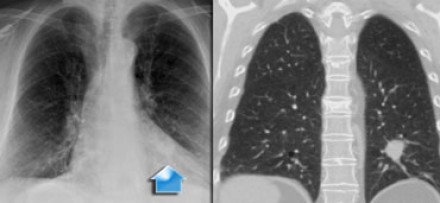

N3 - стадия При N3-стадии визуализируют контралатеральную медиастинальную или контралатеральной хиларную лимфаденопатию или лимфааденопатию надключичных узлов. Считается нерезектабельным состоянием. |

На снимках представлены два пациента с раком легких и лимфаденопатией на

стороне поражения и контралатеральной стороне. |

N3-стадия При N3-стадии визуализируют контралатеральную медиастинальную или контралатеральной хиларную лимфаденопатию или лимфааденопатию надключичных узлов. Считается нерезектабельным состоянием. |